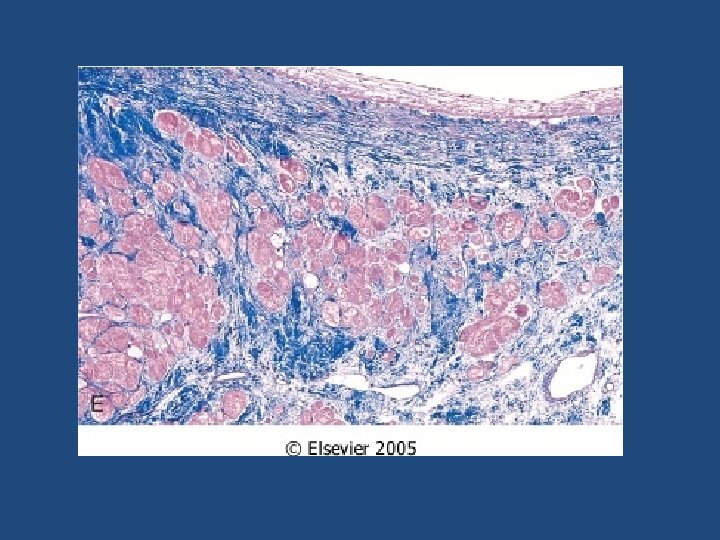

Ischemic Heart Disease MI types • Transmural – Full thickness (>50% of the wall) • Subendocardial – Inner 1/3 of myocardium – Two mechanisms: • Fixed atherosclerosis but with increased demand, vasospasm or hypotension OR • Evolving transmural with relieve of the obstruction (often multifocal)

Ischemic Heart Disease Complications of MI • At least 80% will suffer: – Cardiogenic shock (>40% infarct of LV) – Congestive heart failure. CHF – Arrhythmia – Rupture of ventricle, free wall, septum, or papillary muscle – Aneurysm formation, – Mural thrombus, potentially source of emboli – Pericarditis